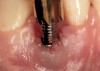

The following case report provides an example of this case scenario: A 24-year-old white male presented with congenitally missing tooth No. 26 restored with a single-tooth cement-retained implant restoration. The implant was placed excessively to the facial aspect of the edentulous site and too shallow, and the periodontal phenotype was thin scalloped (Figure 32). In an effort to mimic the lost midfacial soft tissues, pink ceramics were used as a cosmetic facade. Even though the restoration was not in the esthetic zone, the patient was highly displeased with the esthetic outcome and sought remediation.

The crown and screw-retained custom abutment were removed, and a surgical cover screw was placed into the implant, thereby allowing spontaneous gingival augmentation in situ (Figure 33 and Figure 34). Note that the lingual aspect of the implant site was significantly more coronal than the labial aspect, which was positive because the defect would be limited to a facial–lingual defect. A fixed RBR bridge was cemented on the adjacent teeth and used as a tooth-supported transitional provisional restoration (Figure 35). A few weeks were allotted to let the soft tissue heal and migrate around the cover screw (Figure 36) to see if there would be complete coverage, thereby allowing a soft-tissue augmentation procedure to be performed with primary flap closure as in clinical scenario No. 2. The major obstacle in achieving a positive tissue response was that the implant depth was also deficient because the implant–abutment connection was at the level of the free gingival margin. It was decided that the best treatment option would be to remove the implant. A high-powered reverse-torque device (Fixture Remover Kit, NeoBiotech, www.neobiotechus.com) was used to remove the implant atraumatically (Figure 38 through Figure 41). The implant socket was allowed to heal for several months not unlike an extracted tooth (Figure 42). A new implant was placed in a better position from both a restorative and esthetic perspective (Figure 43), and after a few months of healing, a new crown was made (Figure 44). A satisfactory functional and esthetic result was achieved (Figure 45 and Figure 46) without employing pink porcelain.

Fig 33. Excessive facial angulation of the implant placement shown with an abutment driver in the access screw hole.

Fig 34. A surgical cover screw was placed in an attempt to decoronate the implant and gain soft-tissue coverage in situ.